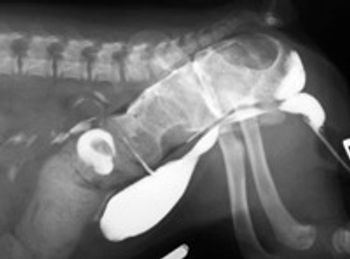

Gastric dilatation volvulus syndrome is an acute medical and surgical condition due to several pathophysiological effects occurring secondary to gastric distension and mal-positioning. It occurs most commonly in large, deep chested dogs.